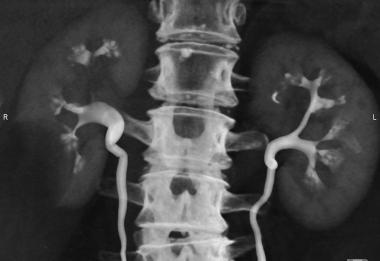

Thực hiện các kỹ thuật chẩn đoán hình ảnh: siêu âm, X-quang, CTscanner, niệu đồ tĩnh mạch…

Khoảng 0,5% bệnh nhân có chụp niệu đồ tĩnh mạch mang bệnh. Ở những bệnh nhân bị sỏi thận, có tới 20% có thể có mức độ nhẹ của xốp tủy thận. Nữ bị nhiều hơn nam, chẩn đoán muộn năm 20-30 tuổi, trung bình là 27 tuổi.